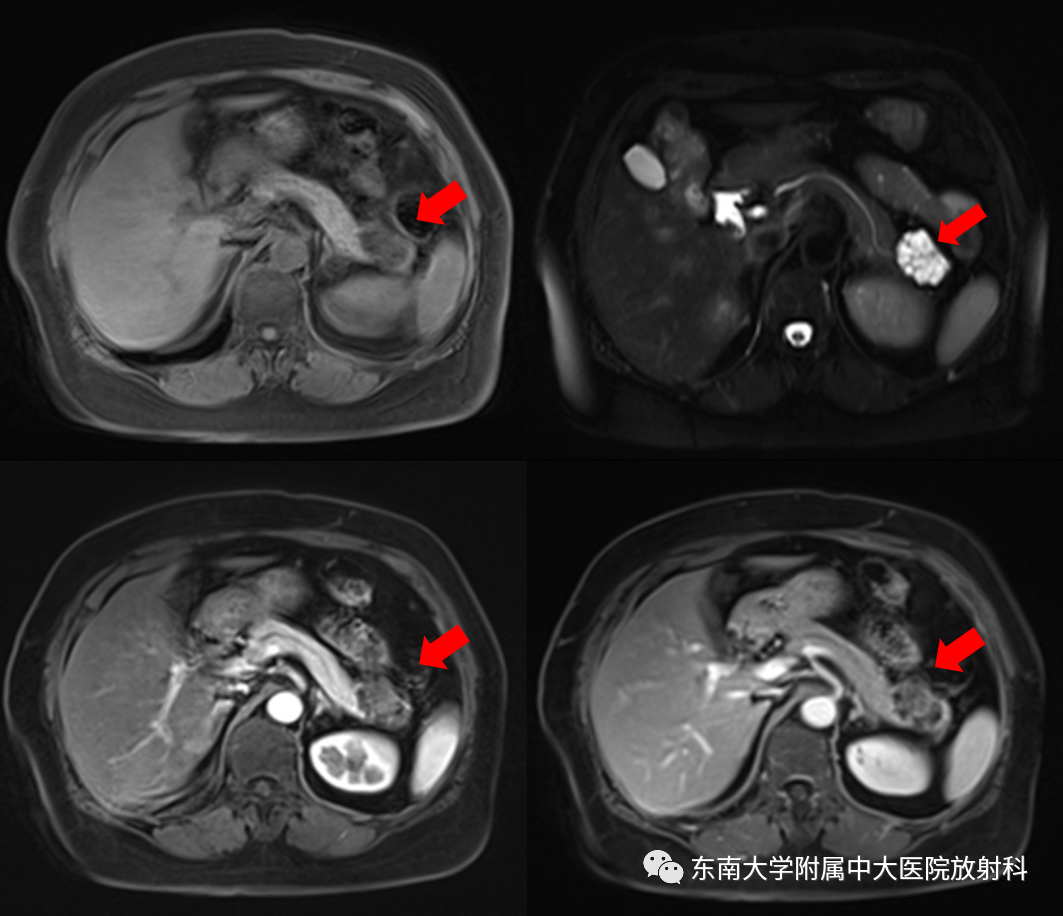

MRI平扫+增强